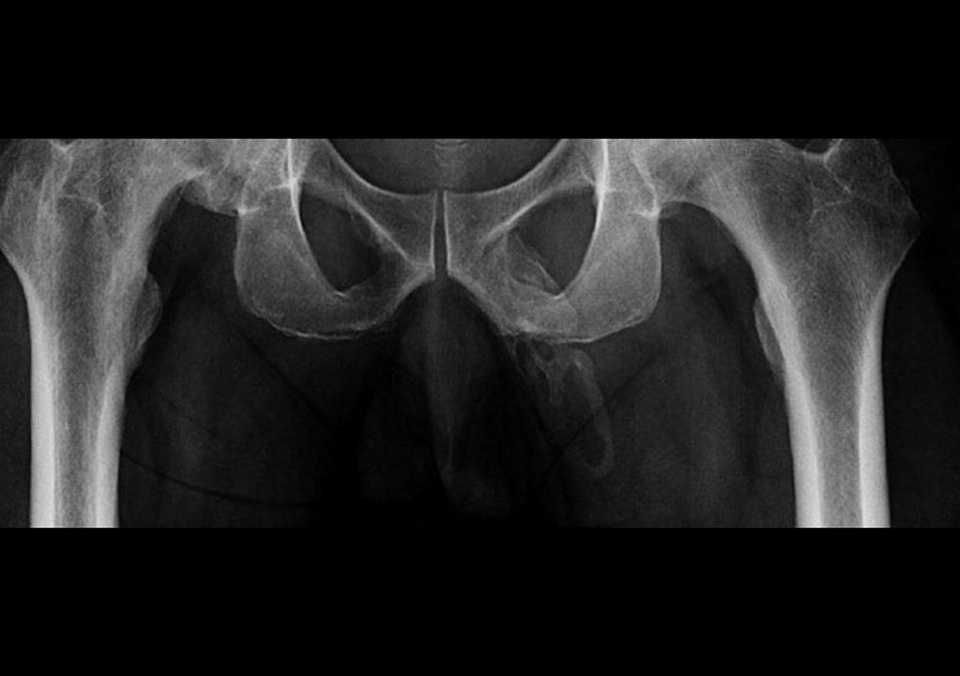

Các bác sĩ đã tìm thấy trường hợp hiếm gặp gây sốc khi họ chụp X-quang xương chậu của người đàn ông để kiểm tra các dấu hiệu gãy xương do ngã. Tuy nhiên, thay vào đó, họ phát hiện ra sự vôi hóa giống như xương ở một nơi thực sự bất ngờ.

Muối canxi đã tích tụ trong mô mềm của người đàn ông và cứng lại thành "một mảng bám rộng" dọc theo toàn bộ trục dương vật.